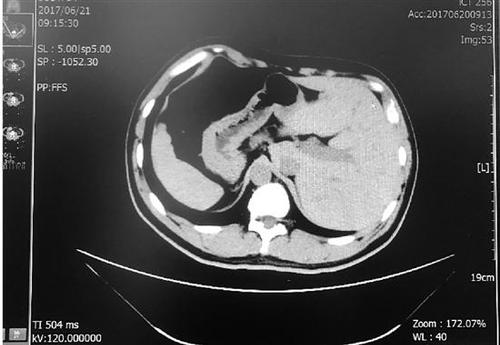

张先生的肝脏在左侧,脾脏在右侧,与正常人相反。

体内的脏器类似于正常人照镜子,五脏六腑的位置与常人相反,过着“颠倒”的人生,这就是我们常说的“镜面人”,发生概率只有百万分之一。

得知需要手术,张先生脱口而出的第一句话就是:“我是个镜面人?!闭庖馕蹲牛男?、肝、脾等脏器都在与常人相反的位置,肠道也是如此?!耙话闳说拇蟪κ撬呈闭氲?,阑尾在右侧,而镜面人的大肠是逆时针方向,阑尾在左侧?!?/p>

“镜面人是完全性内脏反位的俗称,通常表现为胸腔、腹腔器官及解剖结构的完全左右反位?!甭粢绞樯?,“镜面人”是在人体胚胎发育过程中,只有父母体内基因的一个位点同时突变才会出现,这种突变是隐性遗传,遗传几率很低,发生率约为百万分之一。